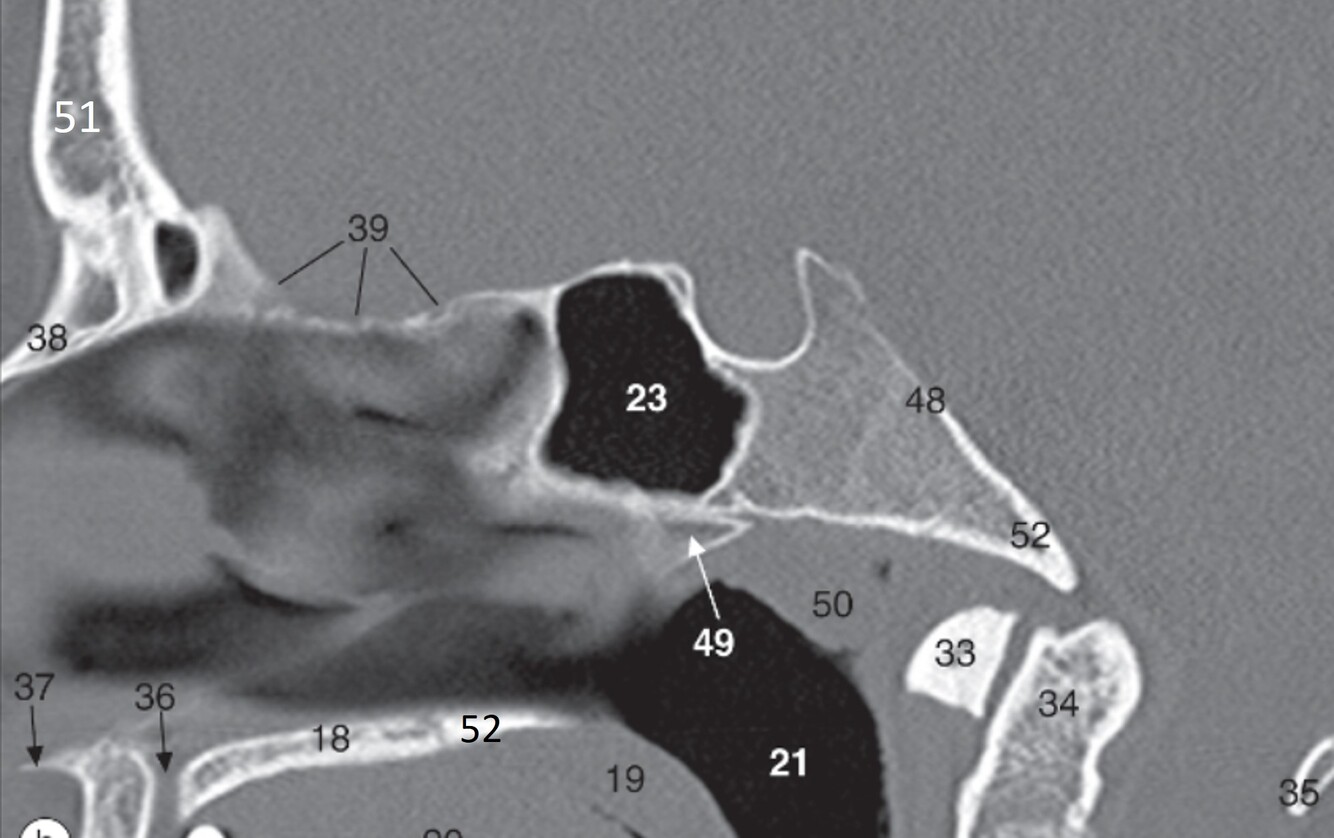

16

Label 35,37,38,39,48

A

35=Posterior arch (C1)

37=Acanthion

38=Nasal bone

39=Cribriform plate (Ethmoid)

48=Clivus

17

Q

Label 49-52

49=Vomer

50=Pharyngeal tonsils

51=Frontal bone

52=Horizontal plate (palatine bone